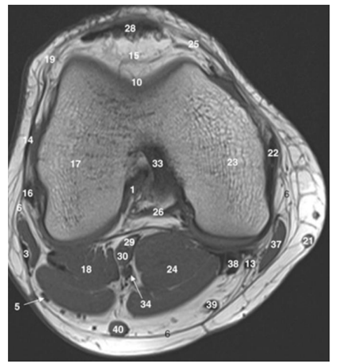

Observe a imagem a seguir.

Os números 17, 23 e 26 na ressonância magnética acima indicam as seguintes estruturas: